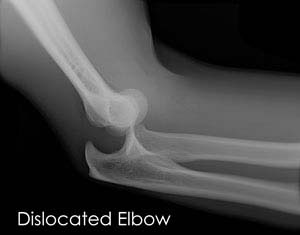

Elbow Dislocation

The arm in the human body is made up of three bones that join to form a hinge joint called the elbow. The upper arm bone or humerus connects...